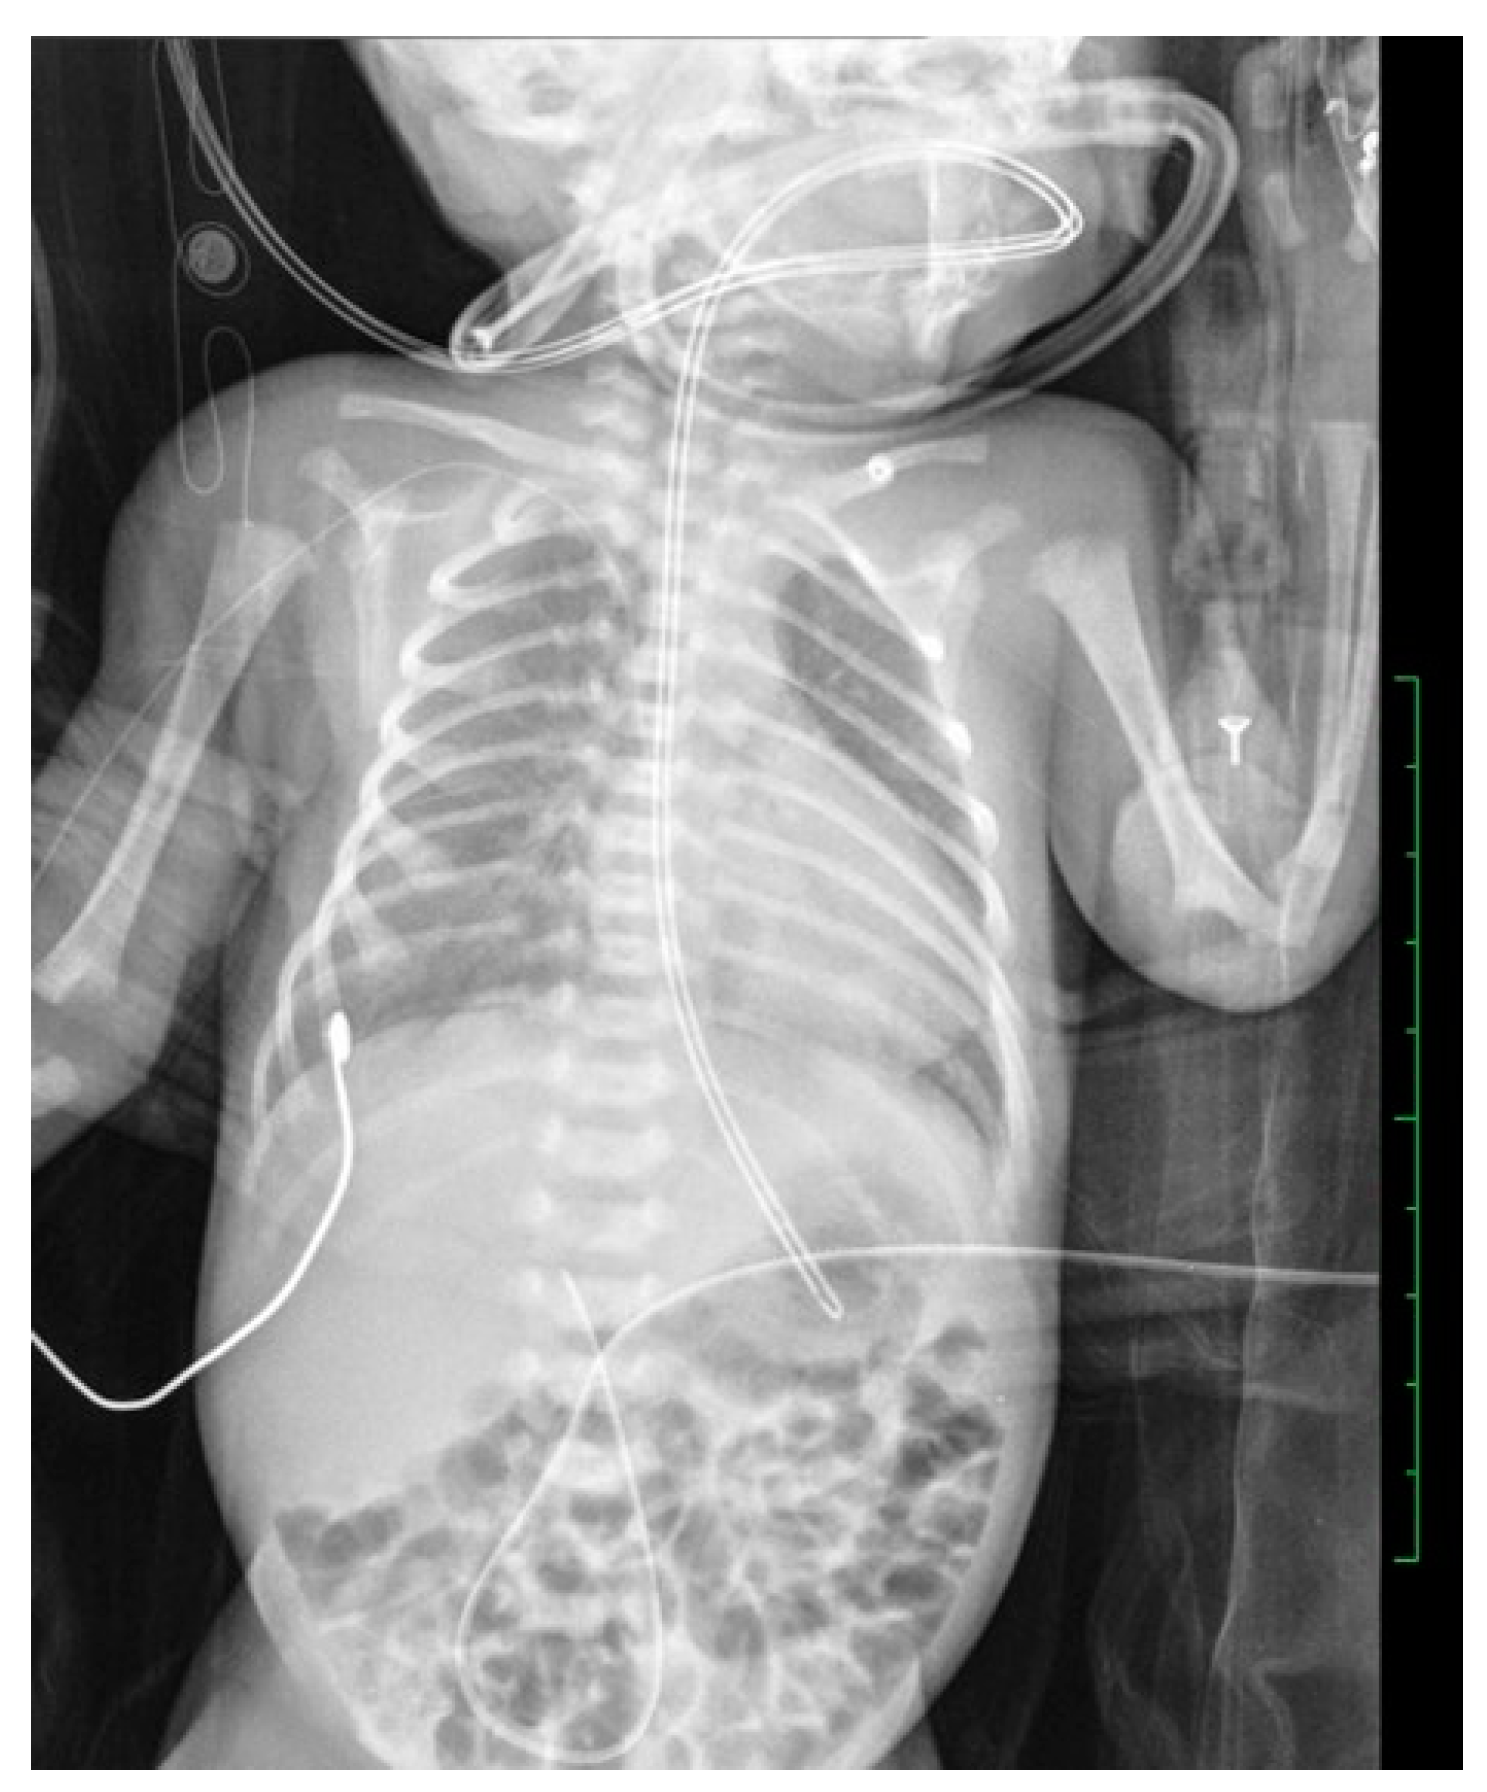

Conventional Radiology Evaluation of Neonatal Intravascular Devices (NIVDs): A Case Series

3. Results